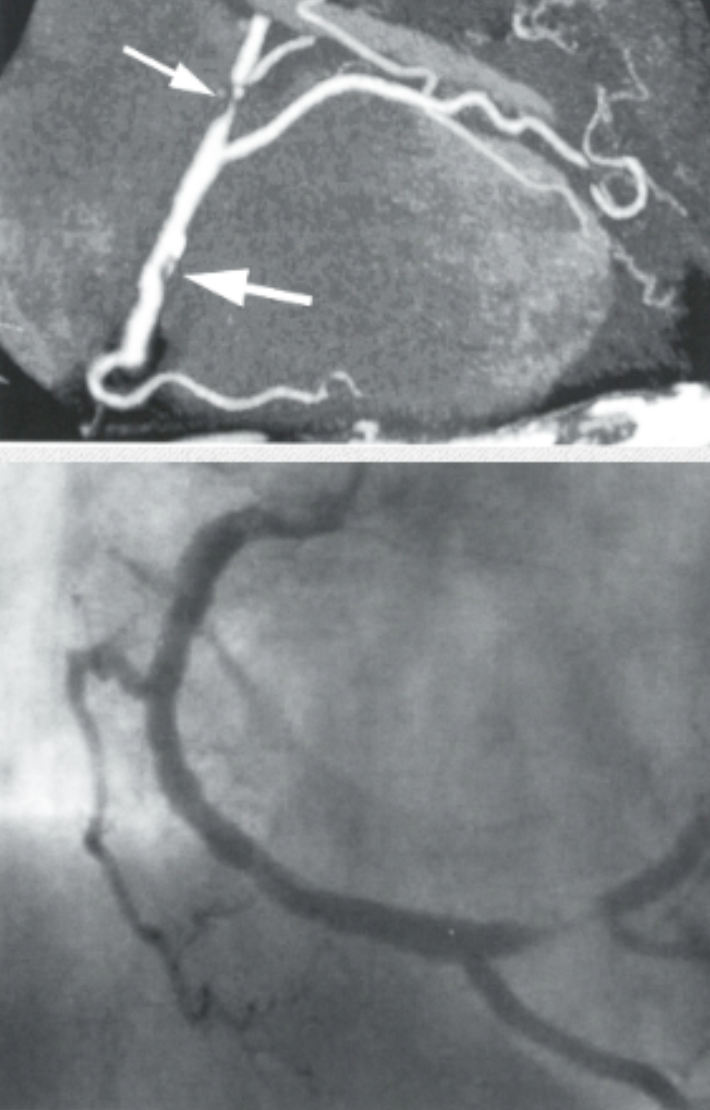

Describe the findings and most likely finding on coronary angiorgram

Occlusion in LCFx territory